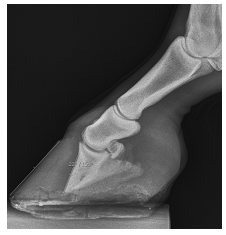

Dadas as afirmativas sobre esse caso,

I. Uma das alternativas terapêuticas é a tenotomia do flexor digital superficial.

II. Rotações de falange distal entre 15 a 20º, se bem cuidadas, têm prognóstico bom e retorno do equino à carreira atlética.

III. Se houver perfuração de sola, uma das alternativas para combater a osteomielite é o fresamento da terceira falange.

verifica-se que está(ão) correta(s) apenas